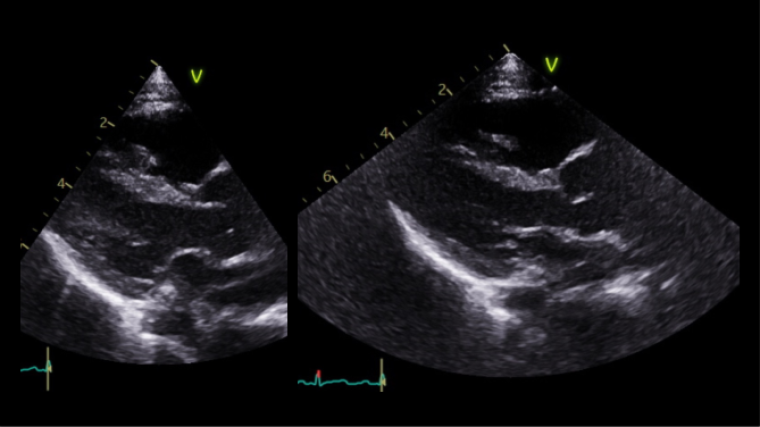

The first echocardiogram was performed when she was 8-month-old showing normal intracardiac anatomy and dimension, mild central aortic regurgitation and a moderate dilatation of the aorta with aortic annulus 13 mm (Z score +0.30), sinus of Valsalva 23.3 mm (Z score +3.71), ST junction 19.2 mm (Z score +3.48) and ascending aorta 19.1 mm (Z score +2.41), Lopez dataset.

A month later she underwent cross sectional imaging. Her CT angiogram head to pelvis showed the aortic root was dilated and the thoracic aorta was elongated at the ascending and arch level, and tortuous with rightwards convexity in the descending portion. Z score Kaiser : sinus 24 x 23 mm (Z score + 4.1), ST junction 18 x 18 mm (Z score + 3.2), ascending aorta 18 x 16 mm (Z score + 3.1), transvers arch 15 x 14 mm (Z score +4.6), isthmus 9 x 9 mm (Z score + 0.5), diaphragmatic aorta 9 x 8 mm (Z score + 0.6). The brachio-cephalic arteries were dilated and tortuous.

She repeated a CT angiogram three years later that showed findings in keeping with her previous one. Z score kaiser : Sinus 26 mm (Z score + 4.7), ST junction 18 x20 mm (Z score + 2.5), ascending aorta 19 x 19 mm (Z score + 2.4), transvers arch 11 x 13 mm (Z score -0.1), isthmus 12.5 x 12.5 mm (Z score + 0.9), diaphragmatic aorta 11 x 11 mm (Z score + 1.1). Figure 4, table 1.